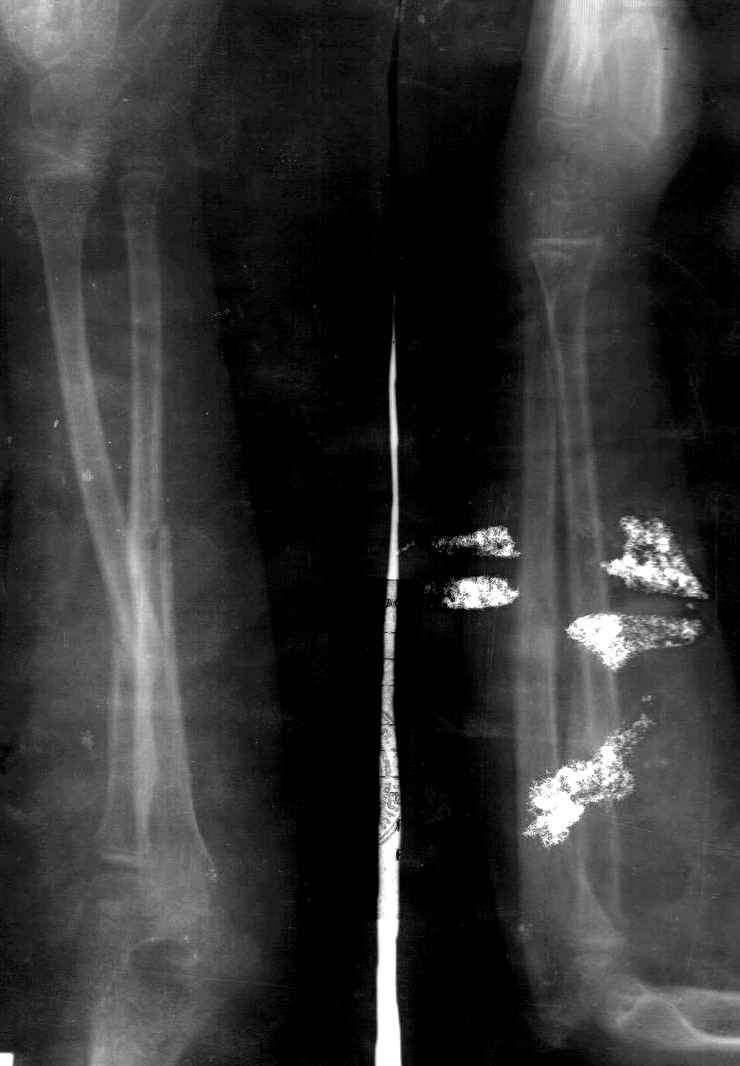

Сделал симметричные снимки с максимальной супинацией и пронацией при согнутом предплечье в 90 град. Объем ротационных движений 90-100 град.

С ув. Сергей Мелашенко

Снимок один сделан с супинацией, второй - оба предплечья в одинаково нейтральном положении. то есть по этим снимкам объем ротационных движений не оценить. Снимко в двух проекциях лучше и делать в среднем положении между пронацией и супинацией, то есть обе проекции в однм и том же положении, когда линия, проходящая через шиловидные отростки, идет в плоскости головки. Прошу прощения за усложнение простых вещей.